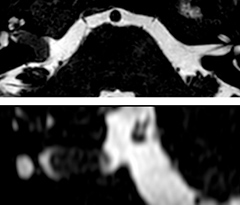

This is an example of acute ischemic stroke with distal occlusion of the right posterior cerebral artery. Note the improved visibility of the ischemic territory on the diffusion weighted image with high b-value. The 3D FLAIR shows a distal PCA occlusion. The fast SWIp depicts the thrombus on the isolated second echo image. The total scan time (including SmartBrain, preparations and a fast 3D T1w TSE Gd) is 8:00 minutes.